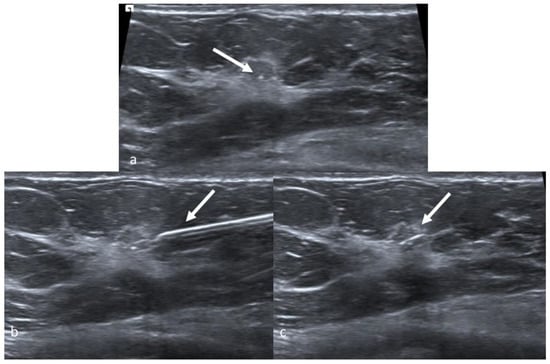

9. Preoperative Localization with a Skin Tattoo